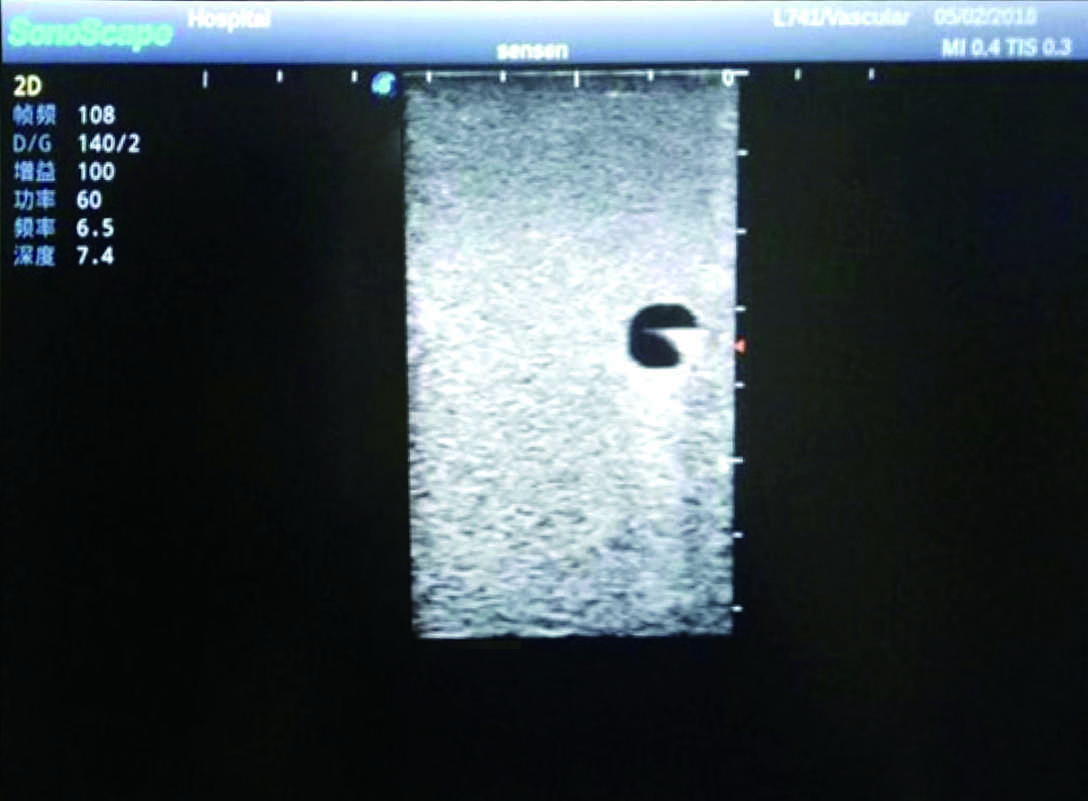

PICC Ultrasound Training Model

Model TYE1510.1

It is a model covering up from lobulus auriculae plane to the umbilical plane, and it has anatomical structures like clavicle, rib, sternocleidomastoid, jugular vein and basilic vein.

1)   Made of high molecular polymer ultrasound material, close to the real skin

2)   It can be used by real ultrasound machines

3)   Clear and real images of the tissues and organs (basilic vein and superior vena cava)

4)   When conducting vascular puncture, the piercing can be truly felt, and venous blood outflow can be seen